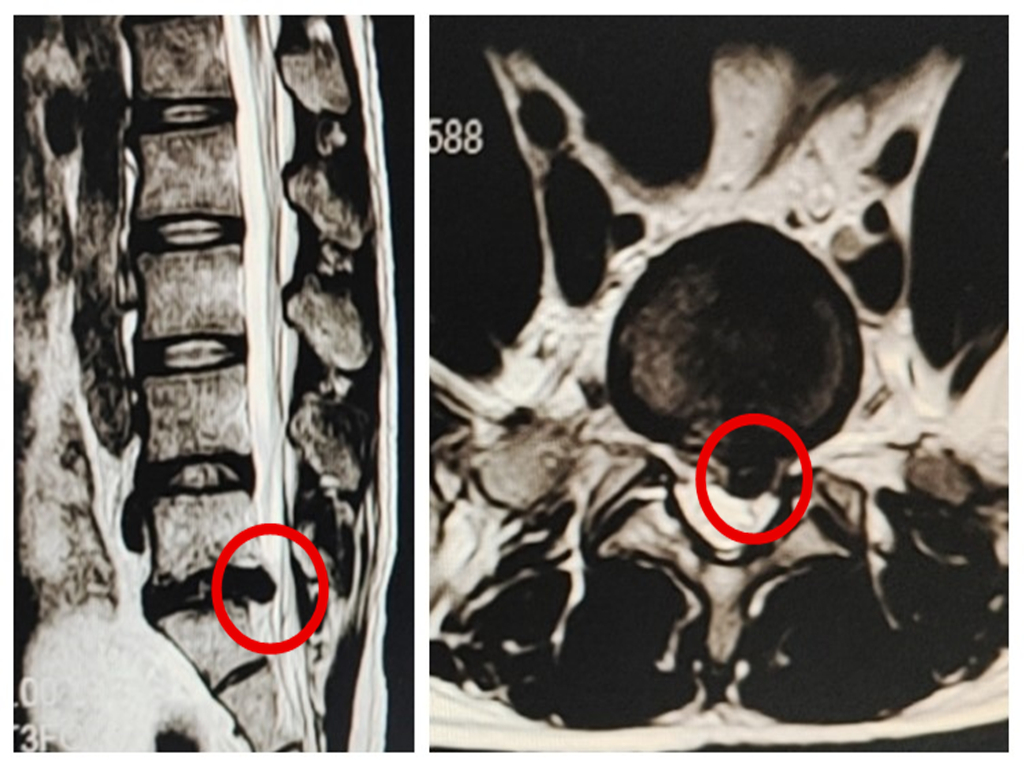

29岁的小何,10余天前在搬货时突然出现腰部及左下肢剧烈疼痛,无法站立、行走,伴左下肢麻木,疼痛难忍,无法睡眠。来到我院骨一科检查。经详细追问,原来小何既往也有腰痛病史,但症状不重,休息后能慢慢好转,这一次搬重物后突然明显加重,并有左下肢剧烈的放射痛。行腰椎磁共振检查发现是腰椎间盘明显突出,并压迫神经根导致了下肢麻木疼痛。

磁共振显示腰椎间盘突出压迫神经根